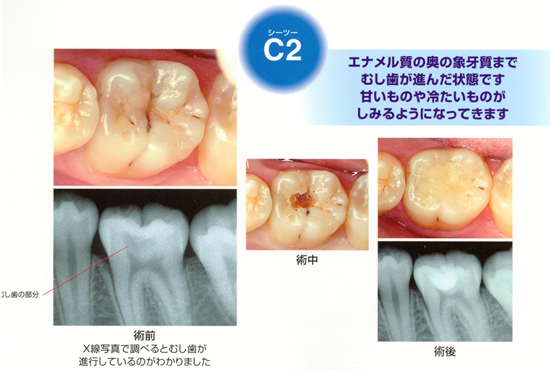

C2(シーツー)

エナメル質の奥の象牙質まで虫歯が進んだ状態です。

甘いものや冷たいものが沁みるようになってきます。